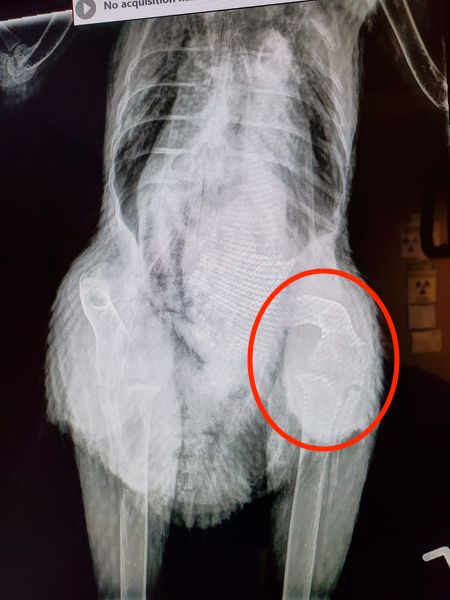

“My 2½ year old Australorp is reluctant to walk, unable to scratch the ground, and has become less social with her flock. The last egg she laid was shell-less about 2 months ago. She eats and poops normally. I am a vet tech and took these x-rays at my clinic but none of the vets I work with know much about chickens. This has been steadily getting worse over the last few months.” – Becky Brooks

Dr Bowes: The femur is obviously badly bowed and is too smooth for it to be a poorly healed fracture. Perhaps the hen had rickets when she was younger or has a metabolic bone disease. The positioning of the x-rays was not ideal (the bad leg is obscured in the last photo) and there was no labeling. It’s possible that there is a pelvic fracture that is not visible, but it’s impossible to assess by looking at the radiographs. The only thing you can offer at this point is pain management.